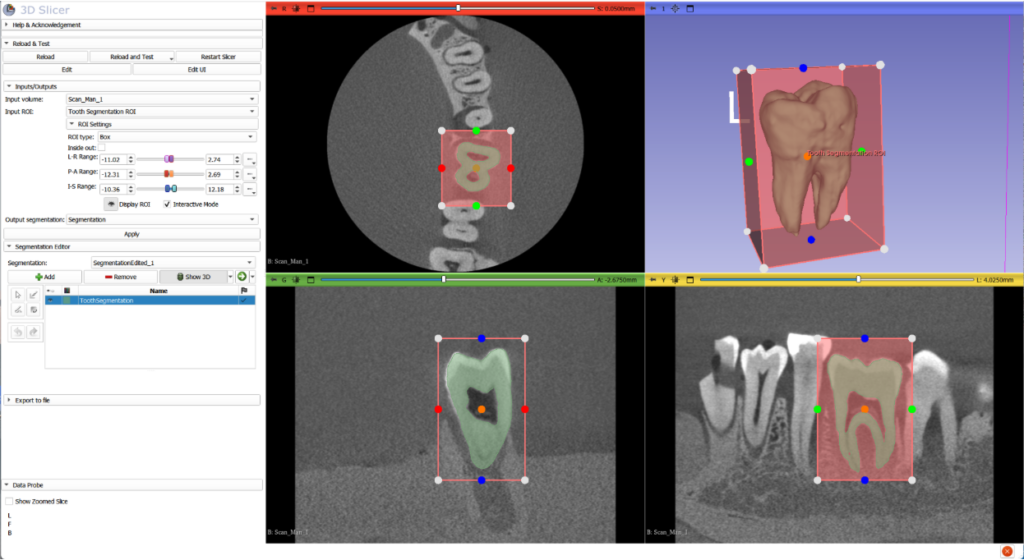

Tooth Detection: Automatic tooth detection continues to be an important focus in digital dentistry. The goal of this task is to isolate teeth in different image acquisition modalities both for internal analysis as well as for understanding their relationship with the surrounding dentition and the rest of the skeleton. Thanks to advances in AI-based image segmentation, there is a large amount of tooling available, both for research and commercial purposes, that allows to accurately isolate and locate teeth in different types of images. Tooth isolation can be challenging in the presence of noisy data that includes acquisition artifacts, low resolution scanners and presence of metal implants. Once the tooth is segmented, it is possible to analyze its internal structure to detect diseases of the dentin and pulp, tissue loss or fractures. It is also possible to study its structure and how it relates to other teeth as well as the maxilla and mandible.

In research, we have contributed to a number of open source toolkits in the field such as SlicerCMF, or DentalSegmentator. These toolkits have assisted researchers in generating groundbreaking findings in Digital Dentistry.